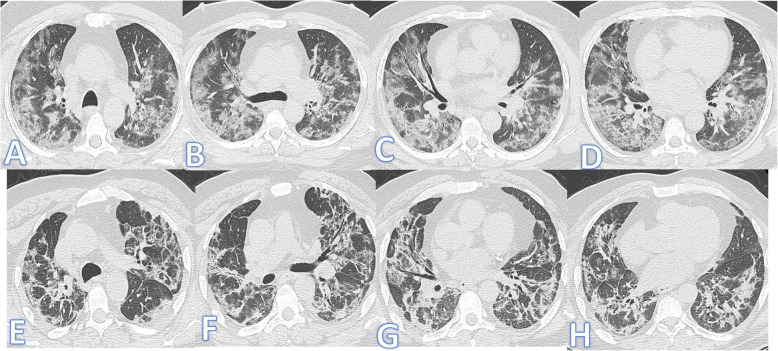

Regarding ICU admission (Figs. 7 and 8), steroid therapy, and length of stay (LOS) in the hospital, there was also a statistically significant difference between both groups (p ˂0.001). The LOS in the fibrotic group was longer than that in the non-fibrotic group (23.26±20.89 vs 8.56±7.03 days). The percentage of ICU admission in the fibrotic group was higher than in the non-fibrotic group (44.6% vs 6.6%).

Fig. 7.

Fifty-five-year-old male: he has DM, HTN, and IHD; peak CT severity score 16; consolidation/crazy-paving score 14. He was admitted to the ICU; laboratory results showed lymphopenia, high CRP, d-dimer, normal serum ferritin, and sensitivity troponin. Steroid was given; length of stay during hospitalization is 30days. Peak CT during admission (a–d) showed bilateral consolidation patches more peripheral and at the lower lobes with a crazy-paving appearance. Follow-up CT 3weeks after discharge (e–h) showed lung fibrosis with parenchymal bands, coarse reticular pattern, irregular interface, and mild traction bronchiectasis at the anterior segments of both upper lobes and the medial segment of the right middle lobe

Fig. 8.

Thirty-nine-year-old male: he has DM and HTN; peak CT severity score 17; consolidation/crazy-paving score 13. He was admitted to the ICU; laboratory results showed lymphopenia, high CRP, d-dimer, and serum ferritin. Steroid was given; length of stay during hospitalization is 20 days. Peak CT during admission (a–d) showed bilateral GGO with mild interstitial thickening and basal consolidation patches. Follow-up CT 2months after discharge (e–h) showed lung fibrosis with parenchymal bands, coarse reticular pattern, and mild bilateral traction bronchiectasis